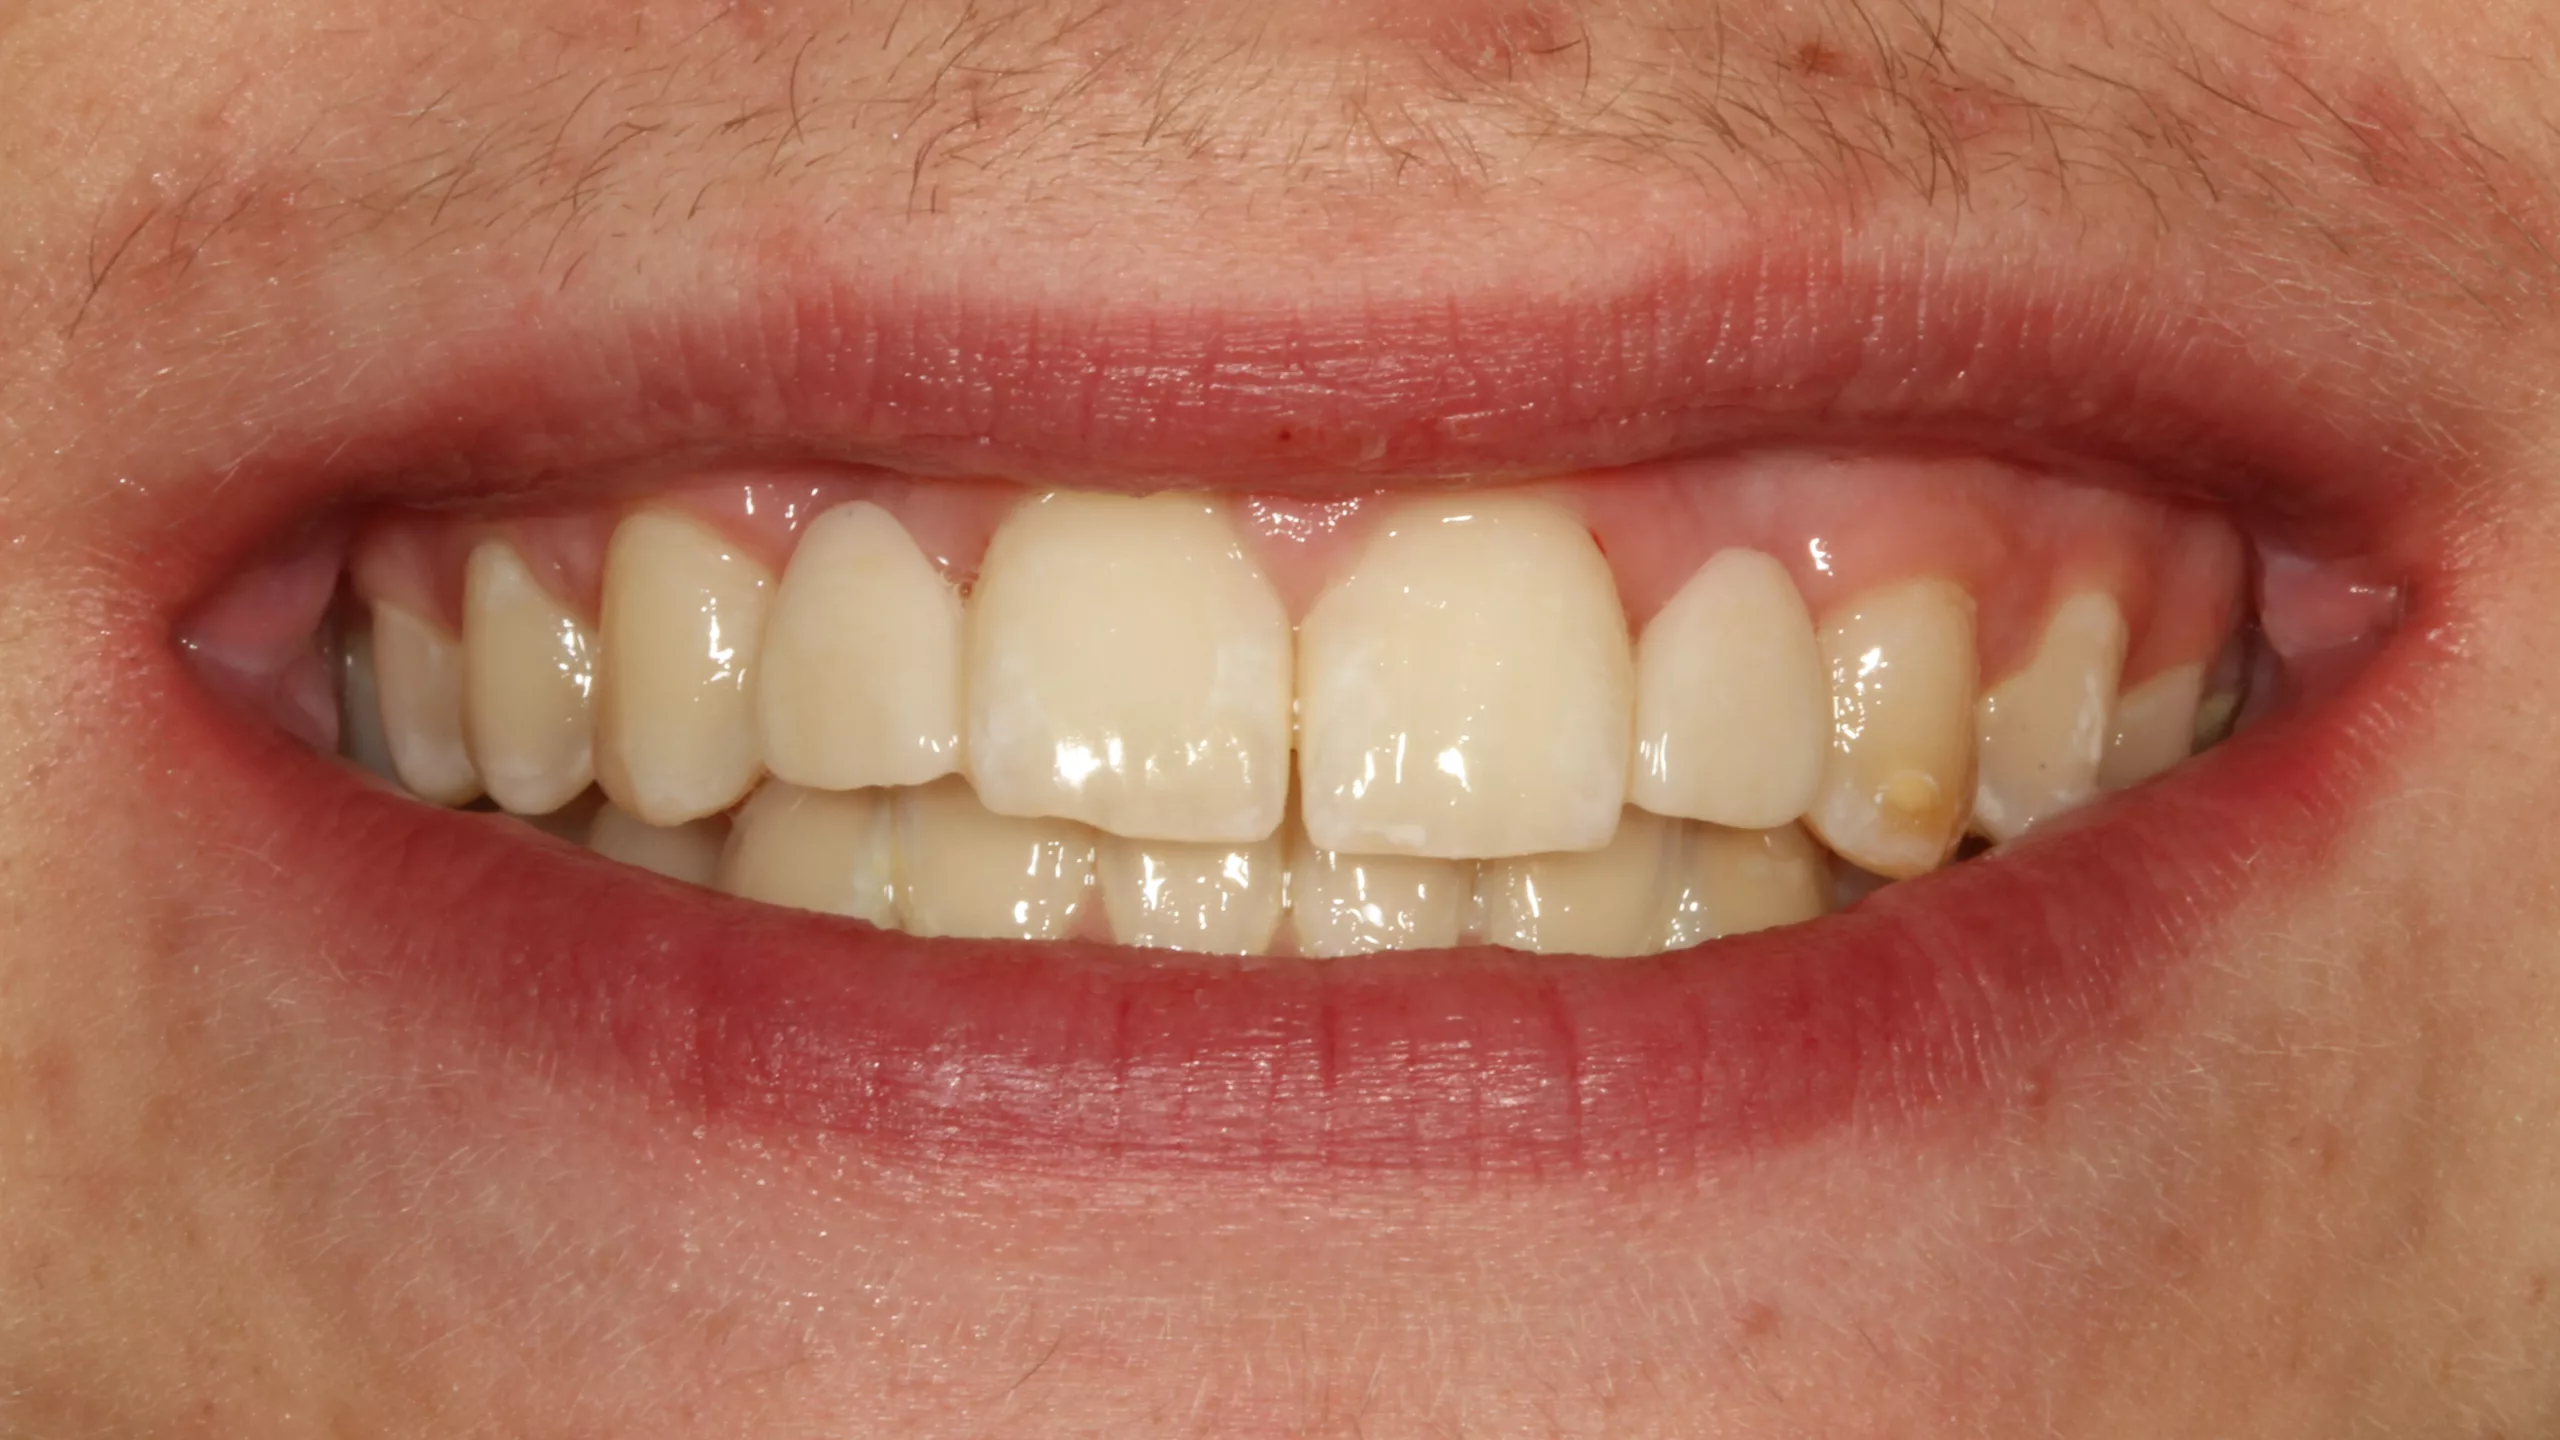

Bei der 55-jährigen Patientin bestand der Wunsch nach einer ästhetischen Neuversorgung ihrer Frontzahnsituation (Abb. 29 und 30). Die Zähne 11 und 22 waren wurzelkanalbehandelt, alle Schneidezähne wiesen ältere, große, farblich nicht mehr passende Kompositversorgungen auf. Die Neuversorgung wurde aufgrund der Stabilität und der besseren Abdeckung verfärbter Zahnbereiche aus einem monolithischen Zirkonmaterial gefertigt, die labial additiv verblendet wurden (Abb. 31 und 32).

Die Abbildungen 35 und 36 zeigen die eingesetzte Arbeit und das zufriedene neue Lächeln der Patientin. Leider konnte im vorliegenden Fall die äußerst dunkle Farbe des Zahnstumpfes von Zahn 22 nicht komplett kaschiert werden. Die Verwendung einer bei Visalys Cem-Core ebenfalls zu Verfügung stehenden, sehr opaken Variante des Materials wurde kurzzeitig erwogen, dann allerdings wiederum verworfen, weil die doch sehr hohe Opazität die Gesamtästhetik vielleicht eher negativ beeinträchtigen könnte. Ein Beispiel zur Verwendung dieses opaken Befestigungs- und Aufbaumaterials zeigt später der letzte Fall dieses Beitrags.